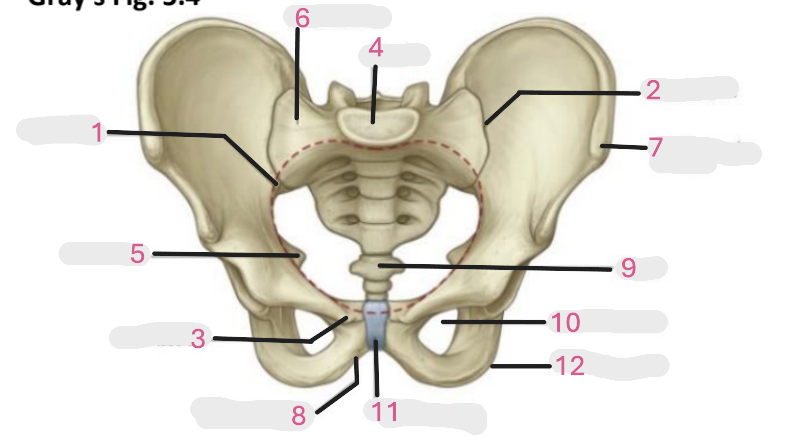

Where is the pelvic inlet

1

Where is the sacro-iliac joint

2

Where is the pubic tubercle

3

Where are the S1 body

4

Where is the ischial spine

5

Where is the ala of sacrum

6

Where is the anterior superior iliac spine

7

Where is the ischiopubic ramus

8

Where is the coccyx

9

Where is the obturator foramen

10

Where is the pubic symphysis

11

Where is the ischial tuberosity

12